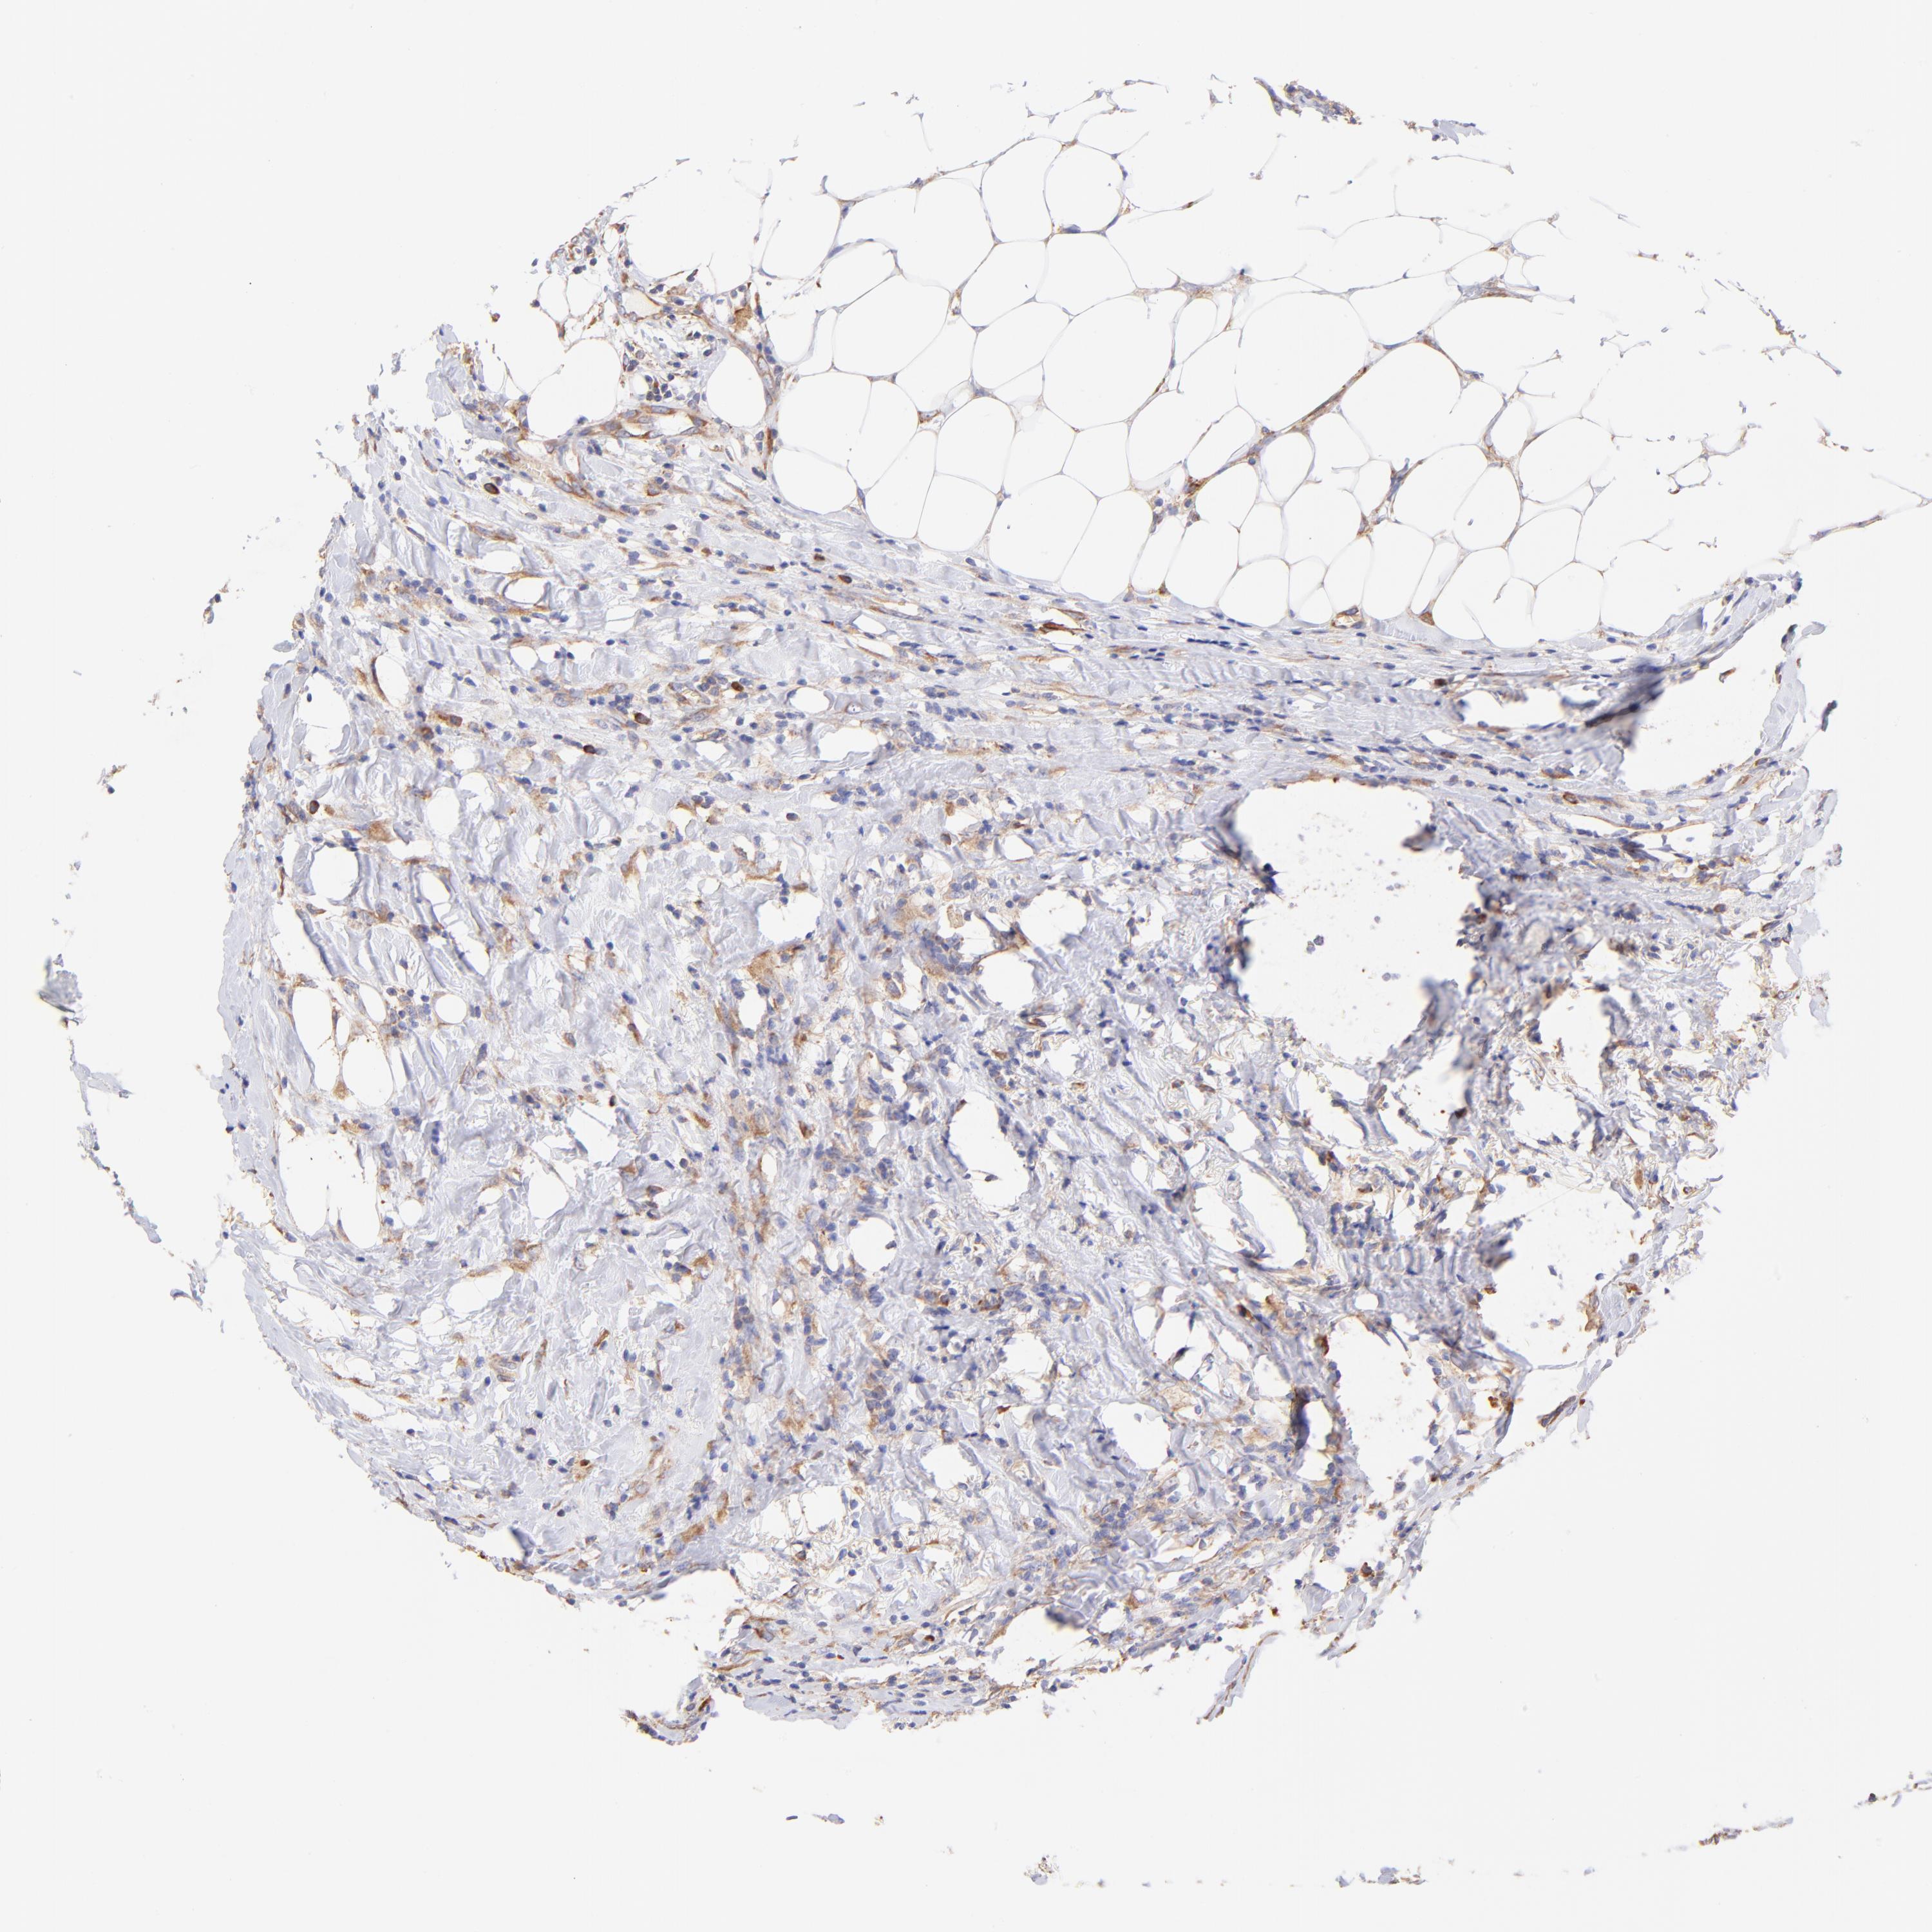

BRCA TCGA BRCA VALIDATION PROTEIN EXPRESSION

ANTIBODIES

AND

VALIDATION